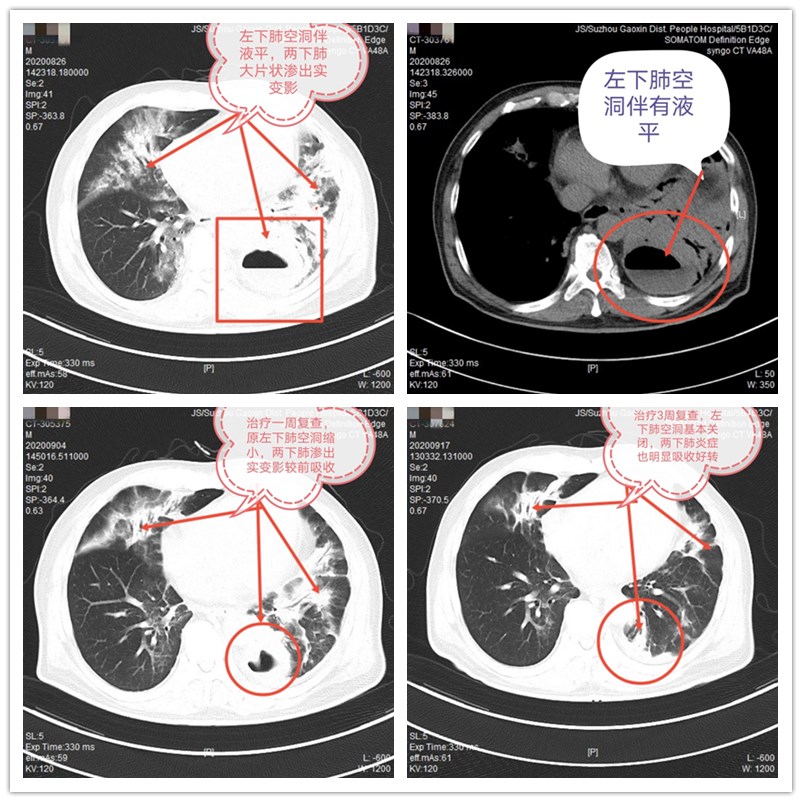

田先生入院以后,关键教授带领诊疗小组医师根据其病情制定了强有力的抗感染方案,胰岛素强化治疗控制血糖,联合保肝、氧疗、防止并发糖尿病酮症、电解质紊乱及增强免疫力等治疗,病情稍稳定及时完善支气管镜检查、行肺泡灌洗、局部保留药物等治疗,同时积极给予了糖尿病饮食健康指导,每日坚持体位引流等。经过20天的治疗,患者病情得到明显缓解,临床症状都消失了,血糖控制达标,炎症指标、肝功能恢复正常,CT示原左下肺脓肿及两肺炎症都吸收好转了,治疗效果非常好。